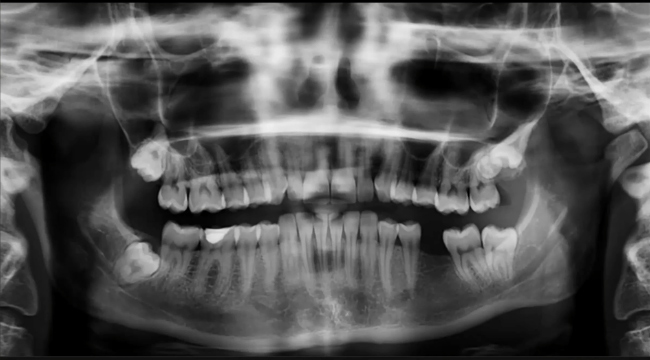

Common inflammatory dental pathologies seen on imaging